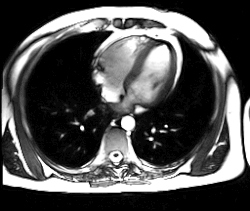

Aplicación en medicina

La resonancia magnética es una técnica que sirve para diagnosticar enfermedades mediante la obtención de imágenes del cuerpo. A pesar de que no existe efecto nocivo sobre el paciente, no se recomienda la práctica en embarazadas, salvo que su uso sea imprescindible.

La máquina que se utiliza en la resonancia magnética, debido a su dimensión y su tecnología, combina las ventajas de los equipos de alto campo magnético y los equipos abiertos. Así, se consigue una mayor definición y una mayor calidad en la imagen, y el paciente tiene una menor sensación de claustrofobia y además tiene una mayor comodidad. La duración de la prueba no depende de la gravedad de la afección, sino que depende de la región que se vaya a estudiar.[cita requerida]